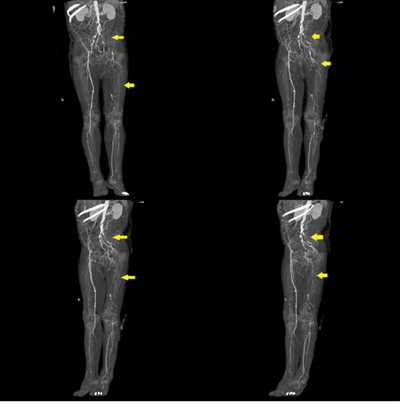

La evaluación laboratorial inicial, solo evidenció un dimero D levemente elevado, no se identificó infección activa ni coagulopatía alguna. El estudio bioquímico no reveló infección viral de hepatitis, lesión renal aguda o algún desequilibrio electrolítico. Mientras que el perfil antifosfolipídico fue normal. En la ecografía doppler se evidenció una oclusión significativa a nivel de arteria femoral común izquierda (Figura 2) y con la angiotomografía contrastada (angio-TAC) (Figura 3), se confirmó la oclusión completa de la arteria ilíaca izquierda con colaterales que proporcionan flujo sanguíneo a ambas arterias iliacas externas y la designación del síndrome como tal, iniciando con antiagregante plaquetario, estatinas y tratamiento por cirugía vascular, debido a la amenaza inmediata de pérdida de la extremidad afectada.

Por ser una patología crónica y progresiva, los pacientes inicialmente pueden estar asintomáticos3 o presentar síntomas inespecíficos; con el desarrollo de arterias colaterales anatómicas como mecanismo compensador, se puede ver retrasada la aparición de los síntomas, dicha compensación surge de los vasos sistémicos o viscerales, lo que conllevaría a una mala perfusión distal8,9. Nuestro paciente, a pesar que refería cuatro meses de enfermedad, la presencia de arterias colaterales en la angio-TAC, nos indicaría dicho mecanismo compensador que muchos pacientes desarrollarían al inicio de la enfermedad.

El síndrome de Leriche se diagnostica a través de estudios vasculares no invasivos, como: la ecografía doppler y la angio-TAC; o estudios invasivos como: la angiografía convencional, siendo éste último, considerado como el estándar de referencia para el diagnóstico8, dichas imágenes nos permiten también definir el sitio de obstrucción, el grado, la presencia de circulación colateral y la permeabilidad distal9,13. En nuestro caso, el diagnóstico fue confirmado con la angio-TAC e inicio manejo multidisciplinario con cirugía vascular, traumatología y medicina interna.